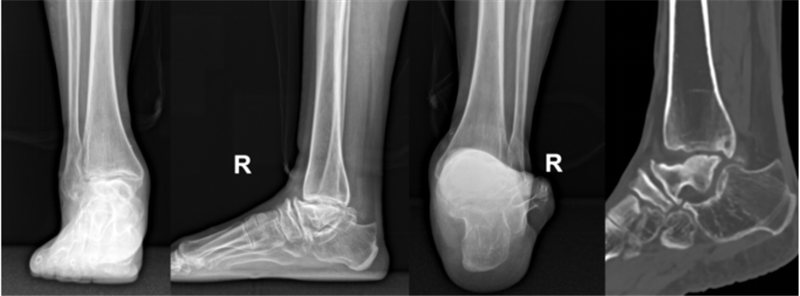

创伤性踝关节炎一例

图片尺寸1920x2560